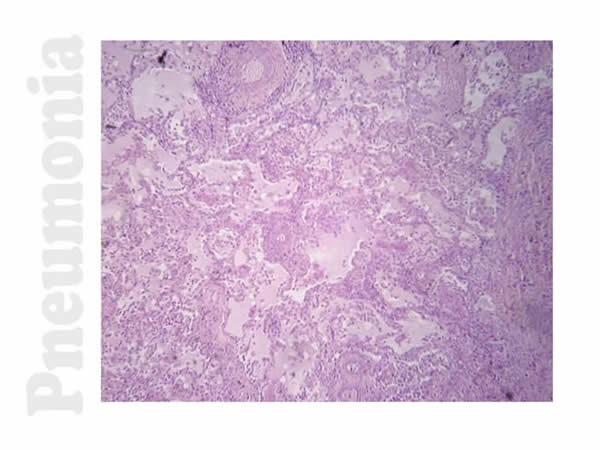

Pneumonia